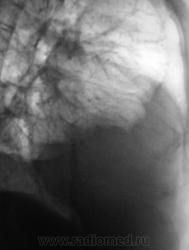

Множественные осумкования в правой плевральной полости жидкости и газа - эмпиема.

Из очевидного - частично осумкованный правосторонний гидроторакс. Неясно, почему правое легкое как бы поддавливает правый контур срединной тени. Нарушение бронхиальной проходимости, клапанная эмфизема? Пациент нуждается в дообследовании.

Конечно же посмотрел бы пациента на УЗД. Больше данных за эмпиему правой плевральной полости.